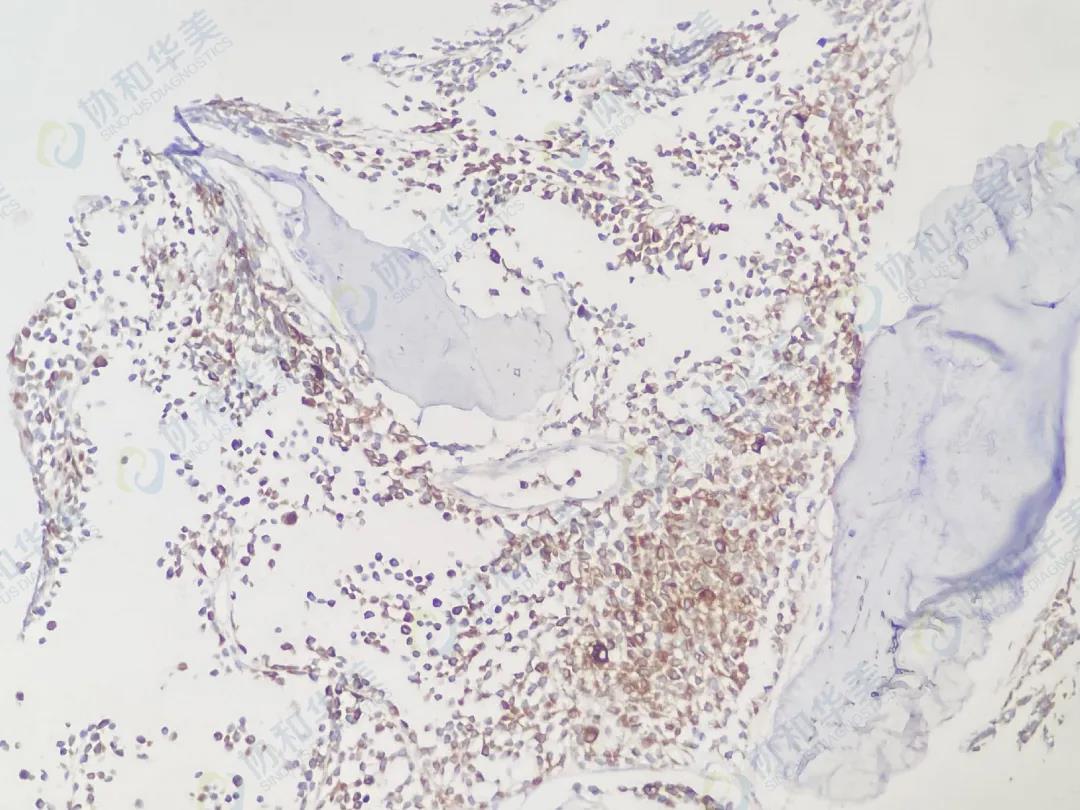

Myogenin